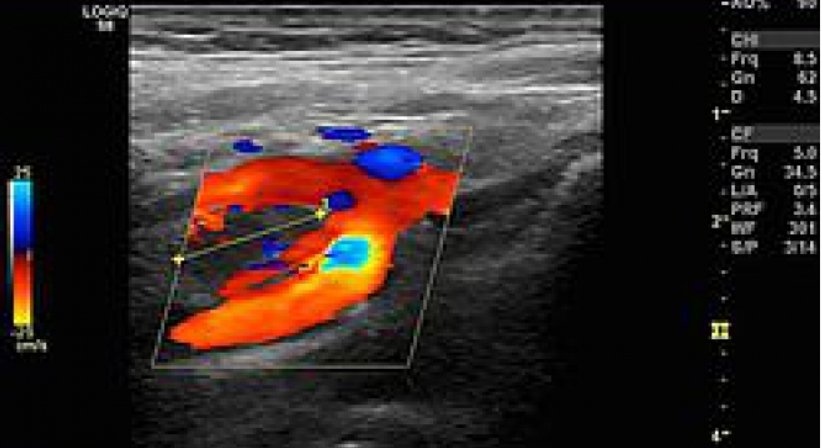

Duplexsonographie der Beinarterien und Beinvenen sind derzeit keine Leistungen der Gebietskrankenkassen und werden privat verrechnet.